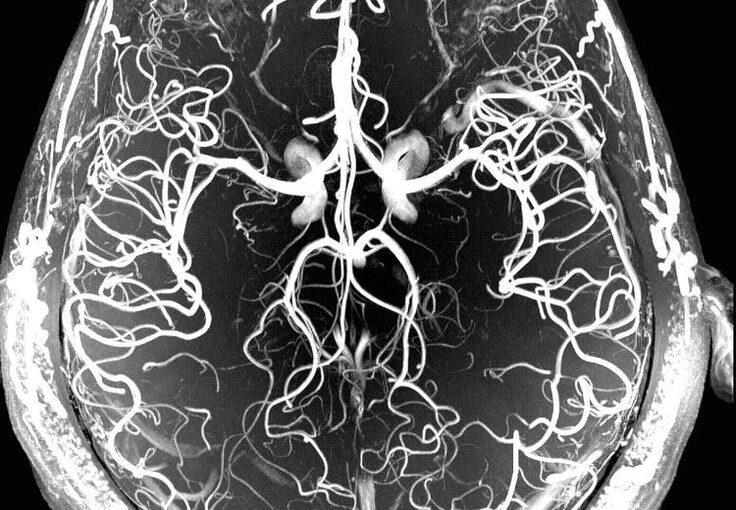

専門診療領域

間脳下垂体疾患、悪性脳腫瘍を含む脳腫瘍、脳血管障害を当科の三つの柱とし、

診断、手術、薬物療法、放射線療法、救急対応まで、

患者さんごとに必要な医療を組み立て、提供しています。